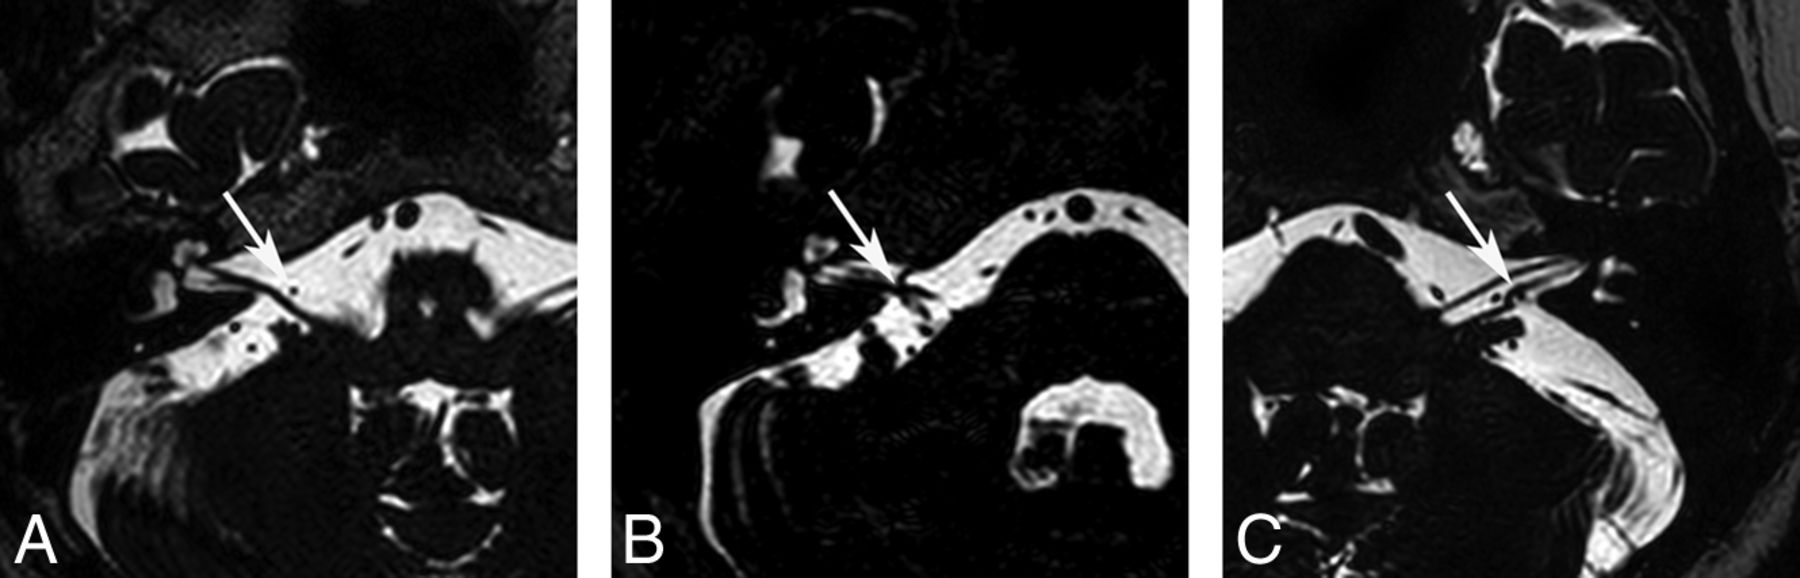

Two neuroradiologists blinded to the clinical findings of the subjects evaluated the neurovascular structures of the IAC and CPA on axial 3D T2-VISTA images and sagittal and/or coronal reconstructed images and made final decisions in consensus. First, the type of AICA loop of all study subjects was determined by using the Chavda classification13 as follows: type I, the AICA loop lying within the CPA but not entering the IAC (Fig 1A and On-line Fig 1A); type II, the AICA loop entering the IAC but not extending >50% of the length of the IAC (Fig 1B and On-line Fig 1B); and type III, the AICA loop extending into >50% of the IAC (Fig 1C and On-line Fig 1C). Second, the type of neurovascular contact was classified into the following 3 categories: type I, no neurovascular contact (Fig 2A and On-line Fig 2A); type II, neurovascular contact present at the cochleovestibular nerve complex but without angulation/indentation of the nerve (Fig 2B and On-line Fig 2B); and type III, neurovascular compression causing cochleovestibular nerve angulation/indentation (Fig 2C and On-line Fig 2C).12 In addition, the presence of neurovascular contact with arterial structures other than the AICA was assessed.

Types of AICA loops. A, Type I AICA loops lie within the CPA (arrow) but do not enter the IAC. B, Type II AICA loops enter the IAC (arrow) but do not extend into >50% of the length of the IAC. C, Type III AICA loops extend into >50% of the IAC (arrow).